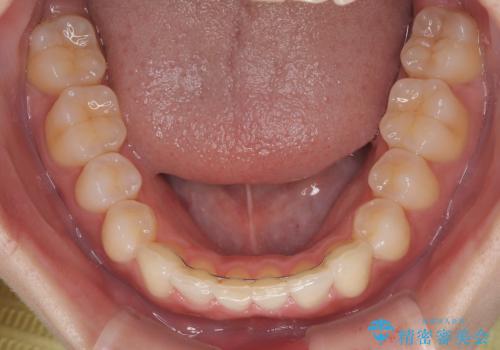

マウスピース矯正特有の、奥歯が噛みにくくなるという現象の解消に少し期間をいただきましたが、日々の装着時間を遵守していただき、綺麗な歯列に整えることができました。